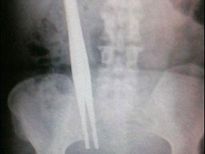

Şoke eden röntgen filmleri

Bu röntgen filmleri görenleri şaşkına çeviriyor!